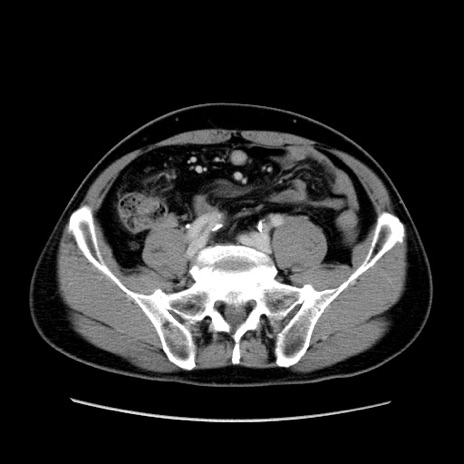

症例34(横断像)

【症例】60歳代 男性

【主訴】右鼠径部膨隆

【現病歴】1年程前より右鼠径部膨隆あり。自己にて還納可能だったため放置していた。3時間前より右鼠径部の脱出を認め、還納困難となり受診。

【既往歴】高血圧

【身体所見】右鼠径部に小児頭大の膨隆あり。弾性硬であり、用手還納は困難。左鼠径部にも膨隆を認める。脱出はなし。

【データ】WBC 15500、CRP 測定なし